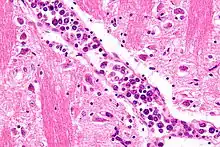

Micrograph showing an intravascular large B-cell lymphoma in a blood vessel of the brain. H&E stain.

The diagnosis of IVBCL is heavily dependent upon obtaining biopsy specimens from involved tissues, particularly the skin but in cases without skin lesions, other apparently involved tissues. Microscopic examination of these tissues typically shows medium-sized to large-sized lymphocytes located within small- to medium-sized blood vessels of the skin, lung, and other tissues or the sinusoids of the liver, bone marrow, and spleen. On occasion, these malignant cells have the appearance of Reed-Sternberg cells. The lesions should show no or very little extension outside of blood vessels. As determined by immunohistochemistry analyses, the intravascular malignant lymphocytes express typical B-cell proteins, particularly CD20, which is found in almost all cases, CD79a and Pax5, which are found in most cases,[5] and MUM1 and Bcl-2, which are found in 95% and 91% of cases, respectively.[2] These B-cells are usually (80% of cases) non-germinal center B-cells (see Pathophysiology section) and may express one or more of the gene, chromosome, and gene expression abnormalities described in the above Pathophysiology section. Since the classical variant can present with a wide range of clinical signs, symptoms, and organ involvements, its presence may not be apparent, particularly in cases that do not exhibit clinically apparent skin lesions. Accordingly, random skin biopsies have been used to obtain evidence of IVL in cases that have signs and/or symptoms of the disease that are restricted to non-cutaneous sites,[2] even in cases that present with no other finding except unexplained fever.[17] The diagnosis of IVBCL, classical variant is solidified by finding these pathological features in more than one site.[2]